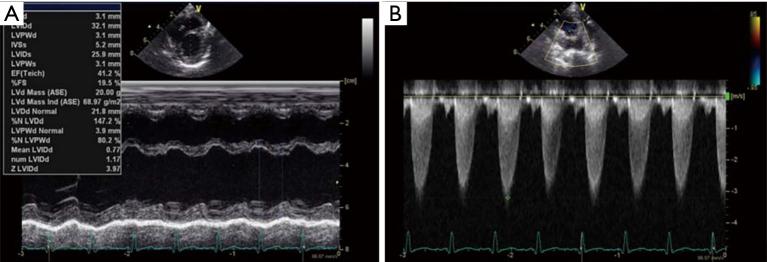

Pulmonary artery banding (PAB) may reduce the need for left ventricular assist devices and heart transplantation in children with end-stage heart failure. However, excessive banding may increase the right ventricular afterload, leading to worsening of heart failure. The estimated right ventricular pressure and the shifting of the interventricular septum by transesophageal echocardiography (TEE), pulmonary artery pressure, right atrial and ventricular pressure, percutaneous oxygen saturation, and mixed venous oxygen saturation are utilized to determine the optimal circumference for PAB. Here, we report the case of a 5-month-old patient with end-stage heart failure due to left ventricular noncompaction cardiomyopathy (LVNC), with a gene mutation of MYH7, who underwent successful PAB. The exact PAB placement was additionally guided by using cerebral regional oxygen saturation (rSO) measurement to achieve a tolerable and optimal PAB effect. We monitored rSO and other hemodynamic parameters while surgeons banded the pulmonary artery to achieve both highest rSO levels and stable hemodynamics. rSO was 68% before banding, and increased and remained at over 90% after the banding at same FiO. Patient's heart failure improved gradually, and the child was discharged home at 6 months after PAB. The rSO is a simple and non-invasive monitor for the measurement of oxygen delivery to the brain tissue. rSO alone would not be able to guide PAB placement in the vulnerable DCM patients, but it may be of one further monitoring value for the optimal pulmonary artery circumference while patients are undergoing PAB.

肺动脉环缩术(PAB)可能会减少终末期心力衰竭儿童对左心室辅助装置和心脏移植的需求。然而,过度环缩可能会增加右心室后负荷,导致心力衰竭恶化。通过经食管超声心动图(TEE)评估右心室压力和室间隔移位、肺动脉压力、右心房和心室压力、经皮血氧饱和度以及混合静脉血氧饱和度,以确定PAB的最佳环缩周长。在此,我们报告一例5个月大的因左心室致密化不全心肌病(LVNC)导致终末期心力衰竭的患者,其存在MYH7基因突变,该患者成功接受了PAB。通过使用脑局部血氧饱和度(rSO)测量来额外指导PAB的精确放置,以实现可耐受且最佳的PAB效果。在外科医生对肺动脉进行环缩时,我们监测rSO和其他血流动力学参数,以实现最高的rSO水平和稳定的血流动力学。环缩前rSO为68%,在相同FiO情况下,环缩后rSO升高并维持在90%以上。患者的心力衰竭逐渐改善,PAB术后6个月患儿出院。rSO是一种用于测量脑组织氧输送的简单且无创的监测方法。单独的rSO无法指导脆弱的扩张型心肌病患者进行PAB放置,但在患者接受PAB时,它可能对确定最佳肺动脉环缩周长具有进一步的监测价值。